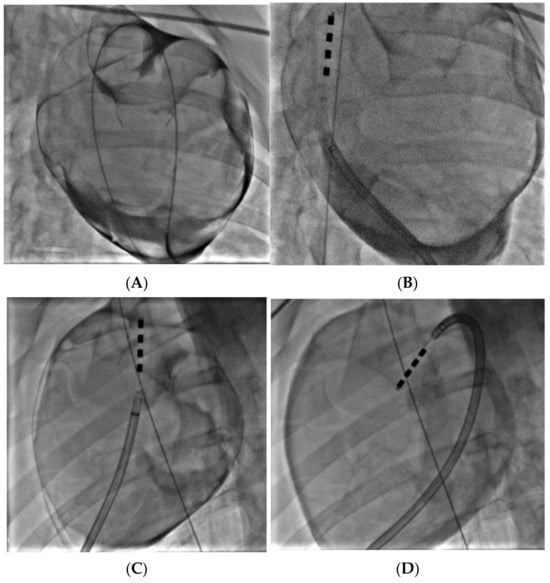

2.5. Porcine Study—Catheter Access and Navigation

3.4. Porcine Study—Catheter Access and Navigation